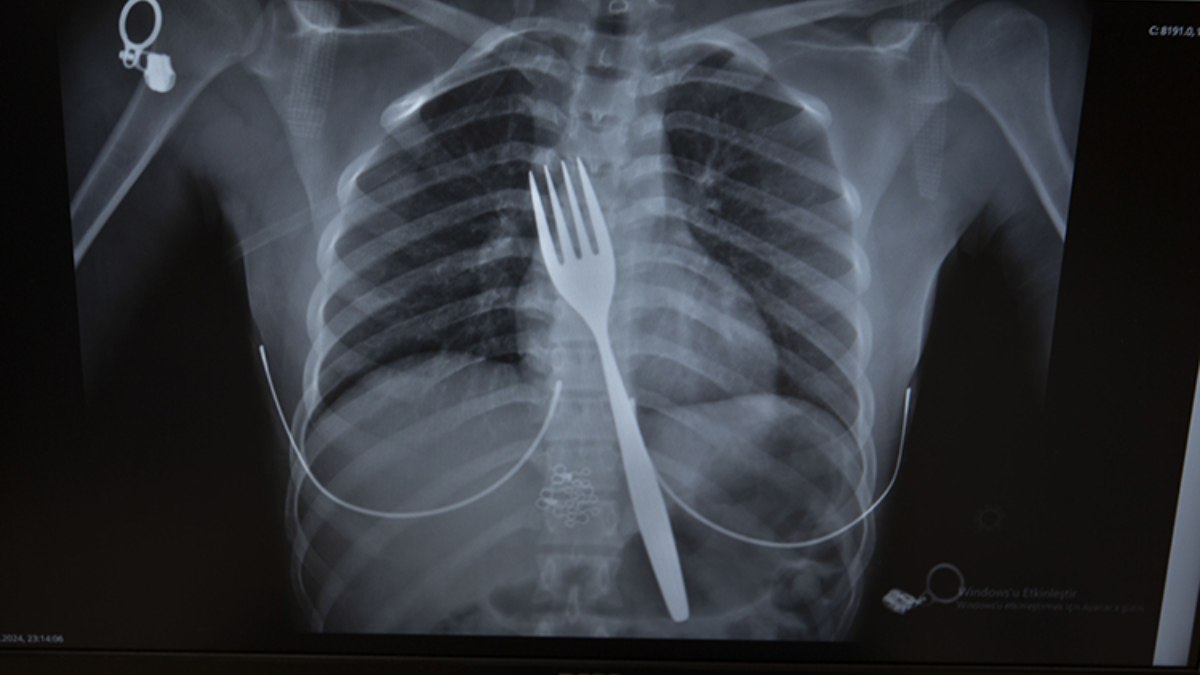

Burada röntgeni çekilen hastanın yemek borusunda 18 santimlik çatal olduğu tespit edildi.

Vakayı ilk duyduğunda şaşırdığını anlatan Edizsoy, “Büyük bir çatalın tamamen yutulması şeklinde ortaya çıkan bu vakayı ilk duyduğumda doğru olmadığını düşündüm. Hasta 18 yaşında ve yabancı uyrukluydu. Türkçesi biraz zayıf olduğu için belki de yanlış anlaşılmalar olabileceğini düşündük. Ama hastanın filmini çektiğimizde gerçekten bir çatalın yemek borusunda olduğunu gördük.” dedi.